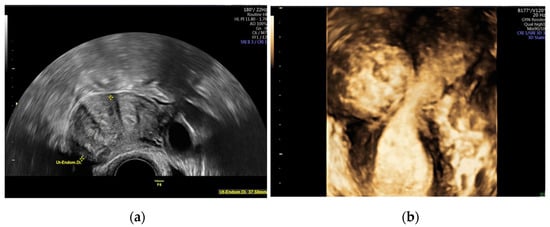

- Seshadri, S.; El-Toukhy, T.; Douiri, A.; Jayaprakasan, K.; Khalaf, Y. Diagnostic accuracy of saline infusion sonography in the evaluation of uterine cavity abnormalities prior to assisted reproductive techniques: A systematic review and meta-analyses. Hum. Reprod. Update 2015, 21, 262–274. [Google Scholar] [CrossRef] [PubMed] [Green Version]

- Andreotti, R.F.; Fleischer, A.C. Practical applications of 3D sonography in gynecologic imaging. Radiol. Clin. N. Am. 2014, 52, 1201–1213. [Google Scholar] [CrossRef]

- Wong, L.; White, N.; Ramkrishna, J.; Araujo Júnior, E.; Meagher, S.; Costa Fda, S. Three-dimensional imaging of the uterus: The value of the coronal plane. World J. Radiol. 2015, 7, 484–493. [Google Scholar] [CrossRef]

- Van den Bosch, T.; Dueholm, M.; Leone, F.P.; Valentin, L.; Rasmussen, C.K.; Votino, A.; Van Schoubroeck, D.; Landolfo, C.; Installé, A.J.; Guerriero, S.; et al. Terms, definitions and measurements to describe sonographic features of myometrium and uterine masses: A consensus opinion from the Morphological Uterus Sonographic Assessment (MUSA) group. Ultrasound Obstet. Gynecol. 2015, 46, 284–298. [Google Scholar] [CrossRef]

- Wozniak, A.; Wozniak, S. Ultrasonography of uterine leiomyomas. Prz. Menopauzalny 2017, 16, 113–117. [Google Scholar] [CrossRef]